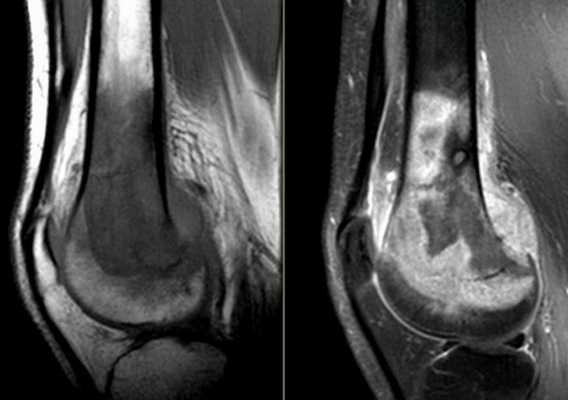

КТ колена

С помощью компьютерной томографии визуализируют нарушения связочного аппарата, костных суставных поверхностей, гиалинового хряща, синовиальной оболочки и капсулы сочленения. Ограничение подвижности и боль возникают чаще при травмах, воспалительных и дегенеративных патологиях.

КТ коленного сустава позволяет диагностировать хондромаляции (разрушение хряща), повреждения менисков, разрывы крестообразных связок. В результате контрастной процедуры выявляют онкологические процессы, заболевания сосудов, липоартрит и пр.